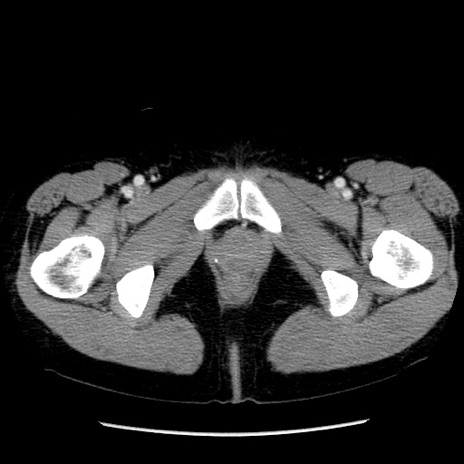

症例6(横断像)

【症例】50歳代女性

【主訴】下腹部痛

【現病歴】本日朝より下痢2回あり。 昼食を食べた後、嘔吐3回、下腹部痛認め、症状軽快せず、当院救急搬送。

最終食事:本日昼(生ものなし)。 昨日の夜、刺身を食ぺたとのこと。周囲に同様の症状の者なし。普段、排便は毎日あるとのこと。

【既往歴】卵巣癌術後(8年前に当院で卵巣摘出)

【身体所見】 意識清明、腹部:平坦、腸蠕動音→、やや硬、下腹部自発痛・圧痛あり、反跳痛あり、筋性防御なし。

【データ】WBC 16000、CRP 0.01